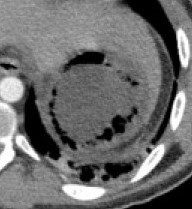

Repeat abdominal CT scan demonstrating complete resorption and disappearance of air from the stomach and the portal venous system (Courtesy Dr. V. Penopoulos)